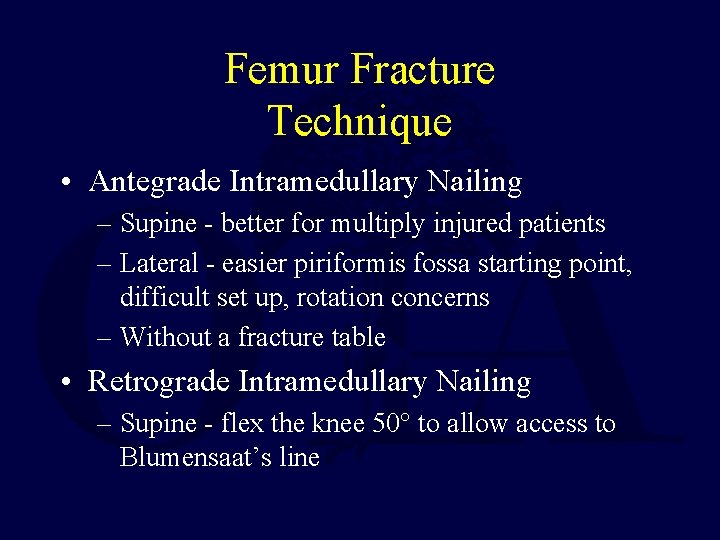

Femur Fracture Technique • Antegrade Intramedullary Nailing – Supine - better for multiply injured patients – Lateral - easier piriformis fossa starting point, difficult set up, rotation concerns – Without a fracture table • Retrograde Intramedullary Nailing – Supine - flex the knee 50° to allow access to Blumensaat’s line